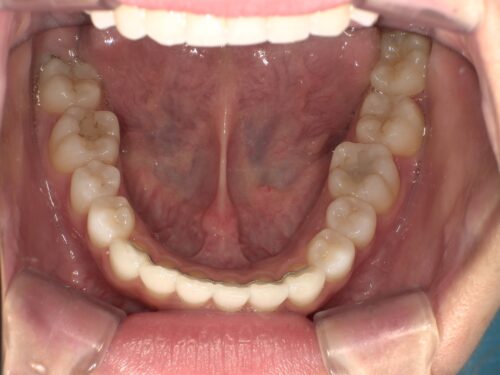

治療後・下顎の写真

下顎のがたつきもしっかり改善されていますね。治療前にあった歯の重なりがなくなり、きれいなアーチ状に並んでいます。